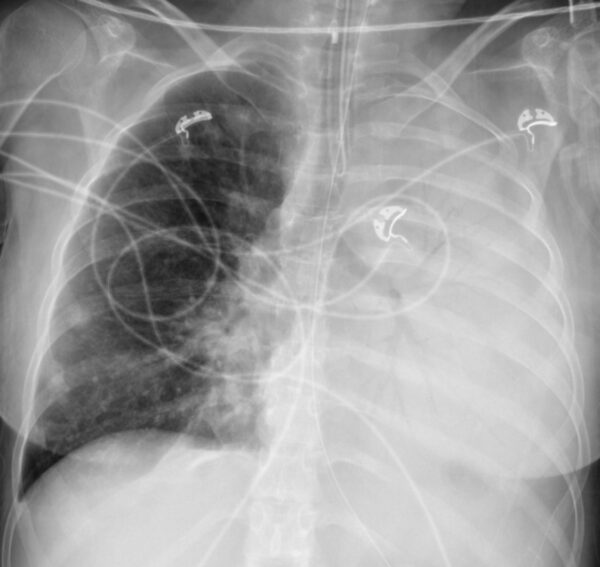

https://radiopaedia.org/cases/hemithorax-white-out-pneumonia-1

X-RAY

CHEST